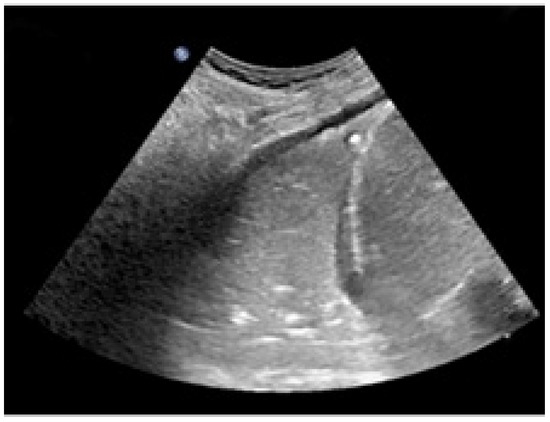

A 19-month-old boy was admitted to the Emergency Department because he fell from his baby feeding highchair. This fall occurred in apparent well-being, without the presence of anticipatory signs or symptoms. First, he fell on his gluteus and then he banged his head (occiput) on the ground. He presented with vomiting (three episodes) and he was very irritable. His respiratory rate and heart rate were >60 breaths and >150 beats per minute, while oxygen saturation was <80%. Upon physical examination, the child was hydrated and conscious, but irritable. More importantly, we noted subcostal retractions, and, at the auscultation, decreased breath sounds in the left basal part of chest. The patient was ventilated with an AMBU balloon connected to an oxygen source and monitored with a pulse oximeter. Despite our intervention, oxygen saturation fell below 70% and the more we ventilated, the more the saturation dropped down. The lung ultrasound (Figure 1) showed the absence of the typical A lines and the consolidation of the lung, which was directly visualized as a solid parenchyma. On the basis of the poor clinical condition, the patient underwent orotracheal intubation with a cuffed endotracheal tube. After the baby was stabilized, he underwent a chest computed tomography (CT) showing complete atelectasis of the left lung with an interruption of the main left bronchus at 12 cm from bronchial bifurcation (Figure 2). An FBA was suspected as the mother also stated that the baby in the previous days had an intensive cough attack and disappeared within 24 h without any treatment. Therefore, a rigid bronchoscopy was performed and an almond of 2 cm in diameter in the main left bronchus was found and promptly removed.

Regarding the radiological presentation patterns occurring in case of FBA, there is current consensus on their variety, although some features have been encountered more frequently [9]. Of the 64 children undergoing chest X-ray, Midulla et al. found localized air trapping (43.6%), atelectasis (40%), mediastinal shift (25.5%), normal radiograph (20%), visible foreign body (9.1%), and pneumonia (5.5%) [1]. However, the use of chest X-ray is controversial because many children have normal chest radiography (up to 20%), while localized air trapping and atelectasis are the most frequent radiological findings (up to 50%) [1]. Pulmonary ultrasound is highly operator-dependent but has the advantage of being X-ray free. Its role in the FBA is limited but could be useful for atelectasis detection. In fact, in the case of our baby, the lack of typical A lines and the presence of a parenchymal echogenicity allowed us in a short time to suspect the presence of a pulmonary atelectasis that could have justified the picture of incipient respiratory insufficiency. Low-dose chest CT is an effective and consistent tool for diagnosing FBA in children, with a sensitivity of 100% and specificity of 98%, so it should be used to prevent unnecessary bronchoscopies [10]. However, the radiological features lack specificity, being fundamental for the diagnosis of rigid bronchoscopy as both its diagnostic and therapeutic role.

Figure 1. Left lung ultrasound showing a consolidation of the lung and the absence of the normal A lines.